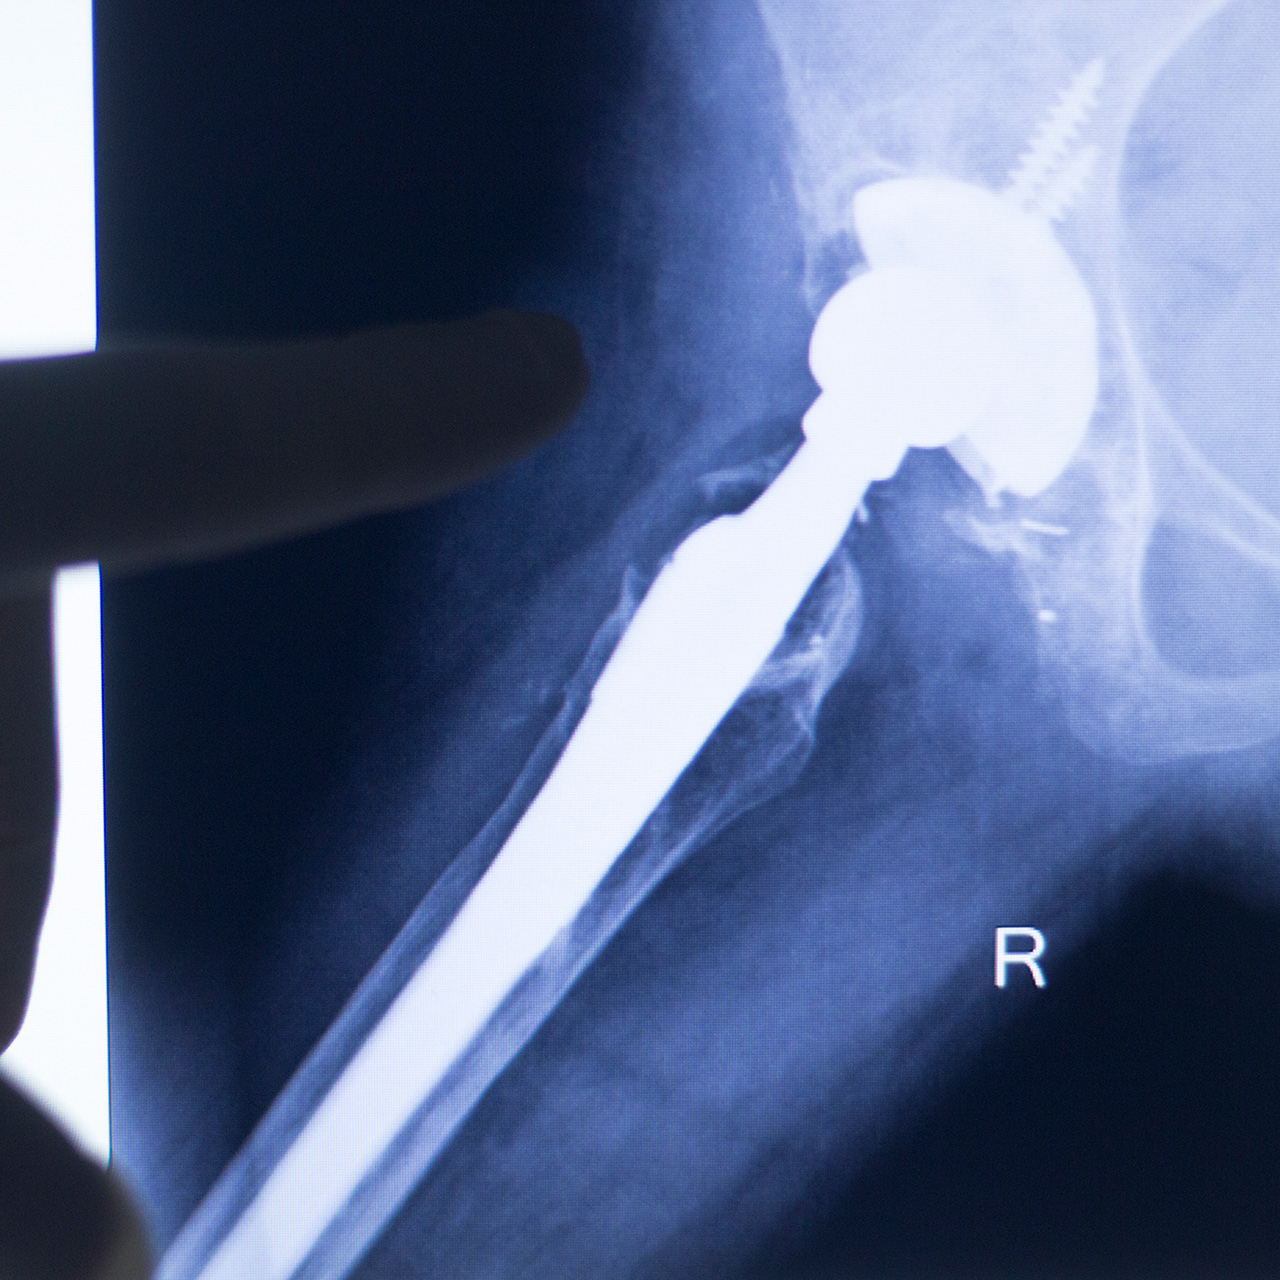

En røntgen av en person

Digital oppfølging etter innsetting av hofteprotese

Innsetting av hofteprotese er en vanlig prosedyre ved sykehusene i Vestre Viken. Tidligere måtte man møte til kontroll på sykehuset seks måneder etter operasjonen. Da ble det tatt røntgenbilder av hoften, man måtte svare på noen spørreskjema og hadde samtale med fysioterapeut. Ved behov ble man undersøkt av lege.

Ny forskning viser at det å ta røntgenbilder etter seks måneder ikke er nødvendig. Dette åpner opp for at oppfølgingen kan skje digitalt, uten at du trenger å møte opp fysisk på sykehuset.